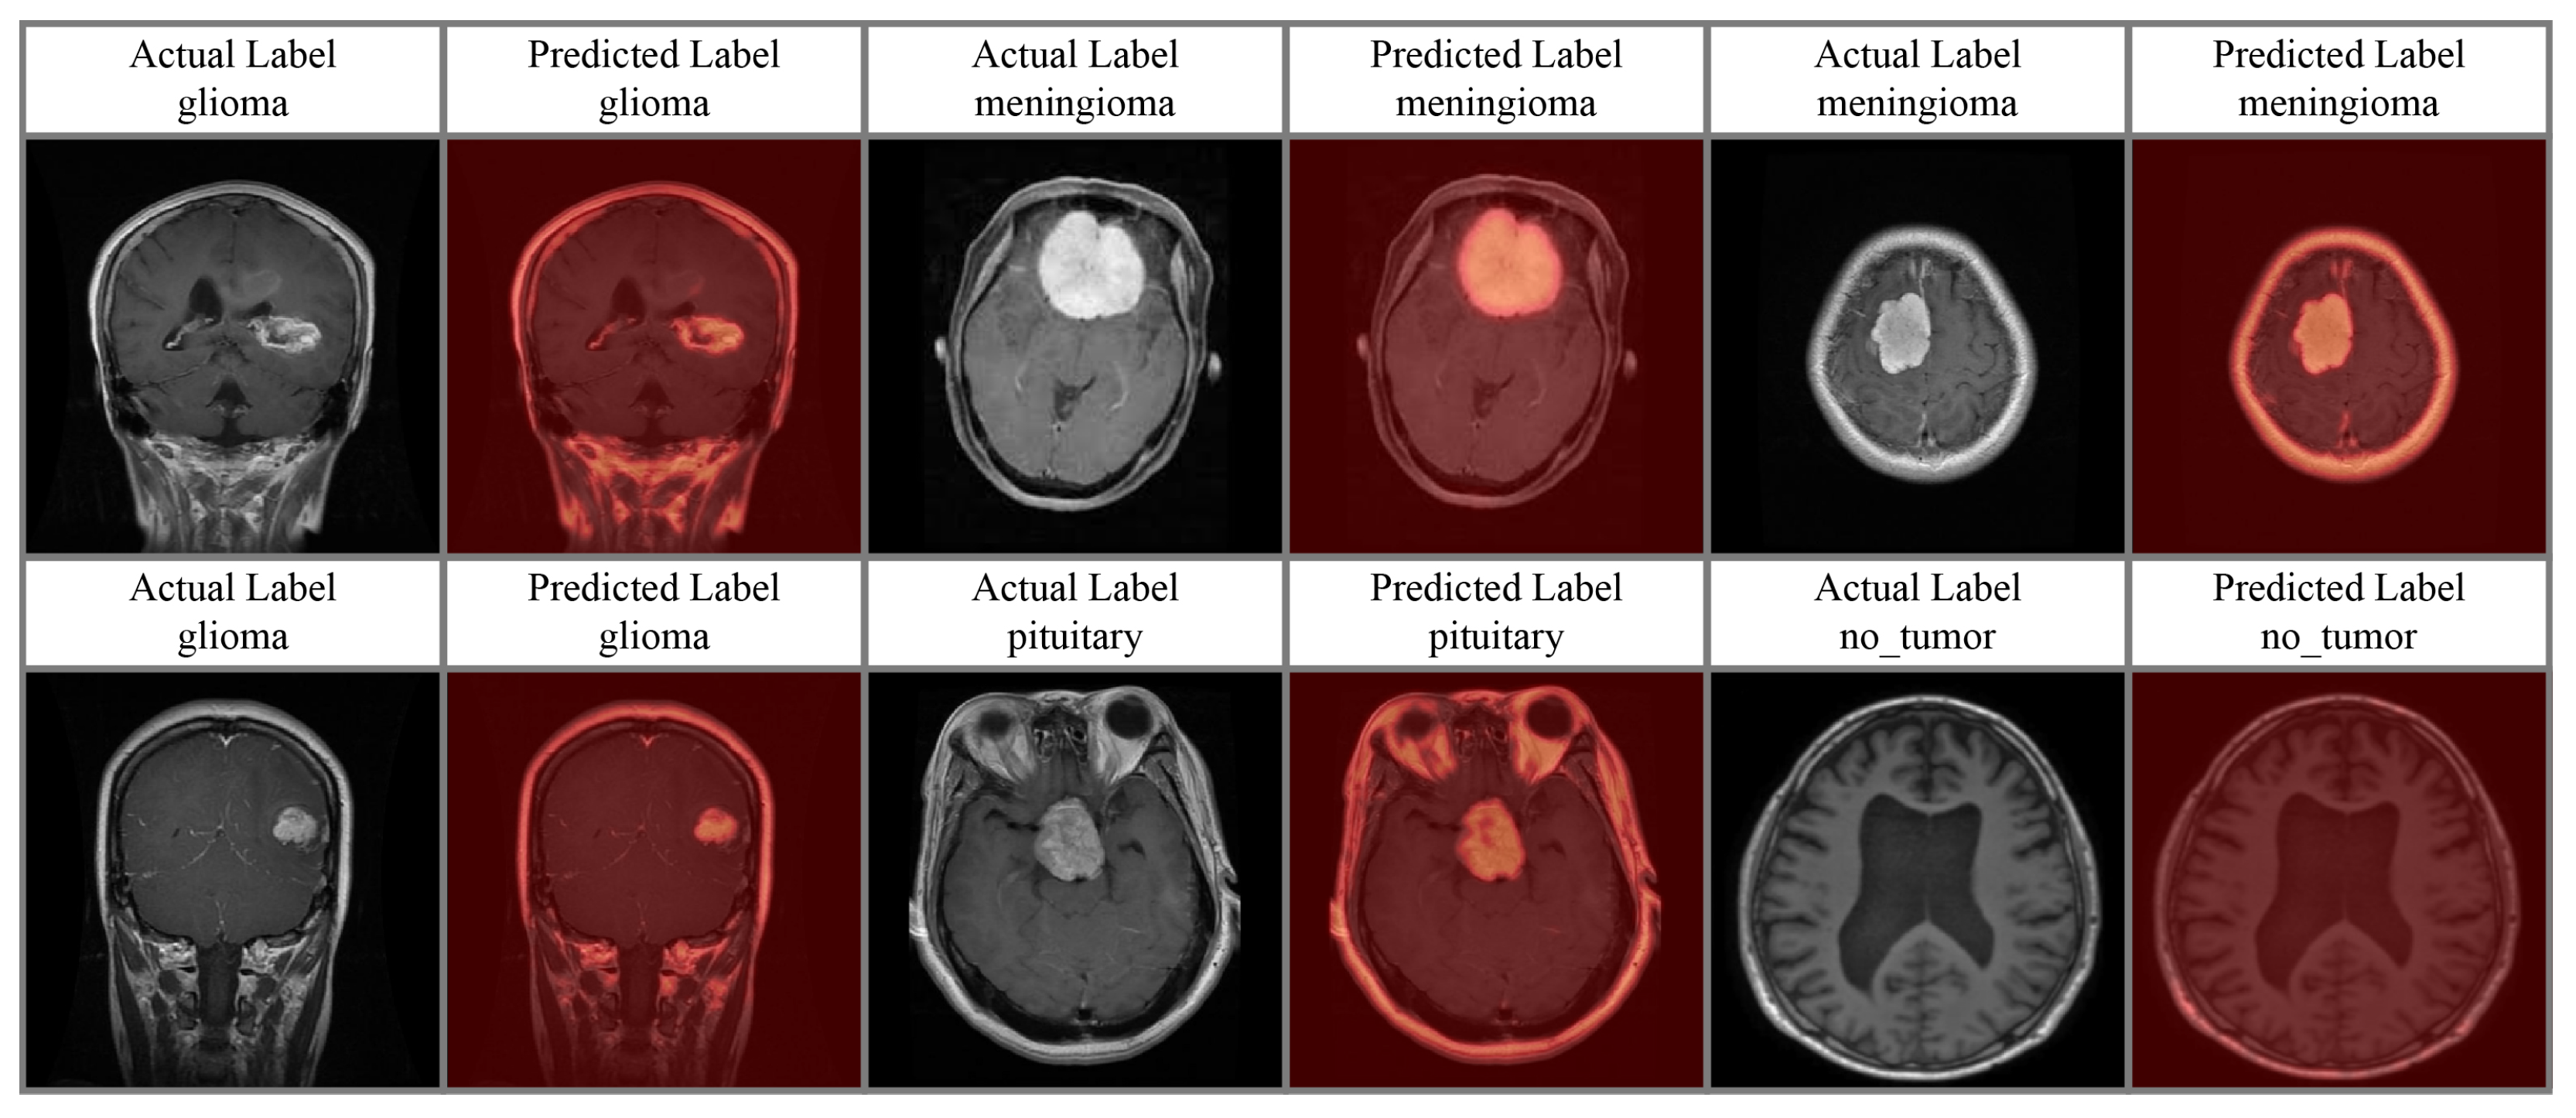

4.4. Attention Analysis